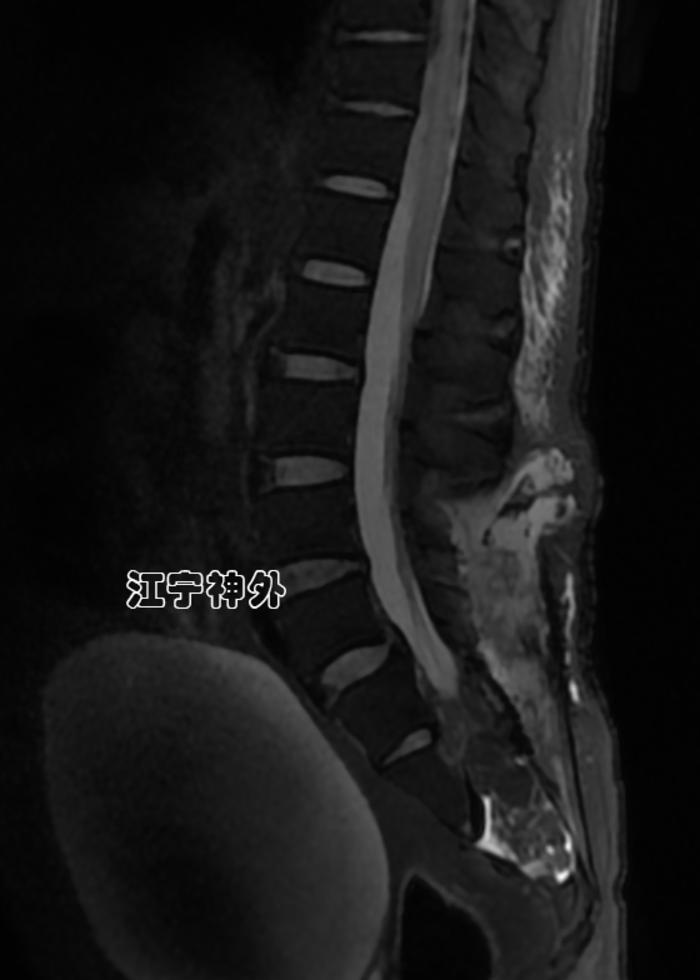

我院术前磁共振检查发现,骶1-3两个巨大骶管囊肿,其中左侧骶管囊肿更大,但症状却是在右侧。

郑主任仔细阅片发现,右侧骶管囊肿虽然比较小,但是其脑脊液漏口处(囊颈)存在一块灰色异常信号,推测可能存在神经根内疝。

术后磁共振显示双侧骶管囊肿封堵良好。并且使用钛板修补了缺损的骶管后壁,避免骶管内容物膨出。